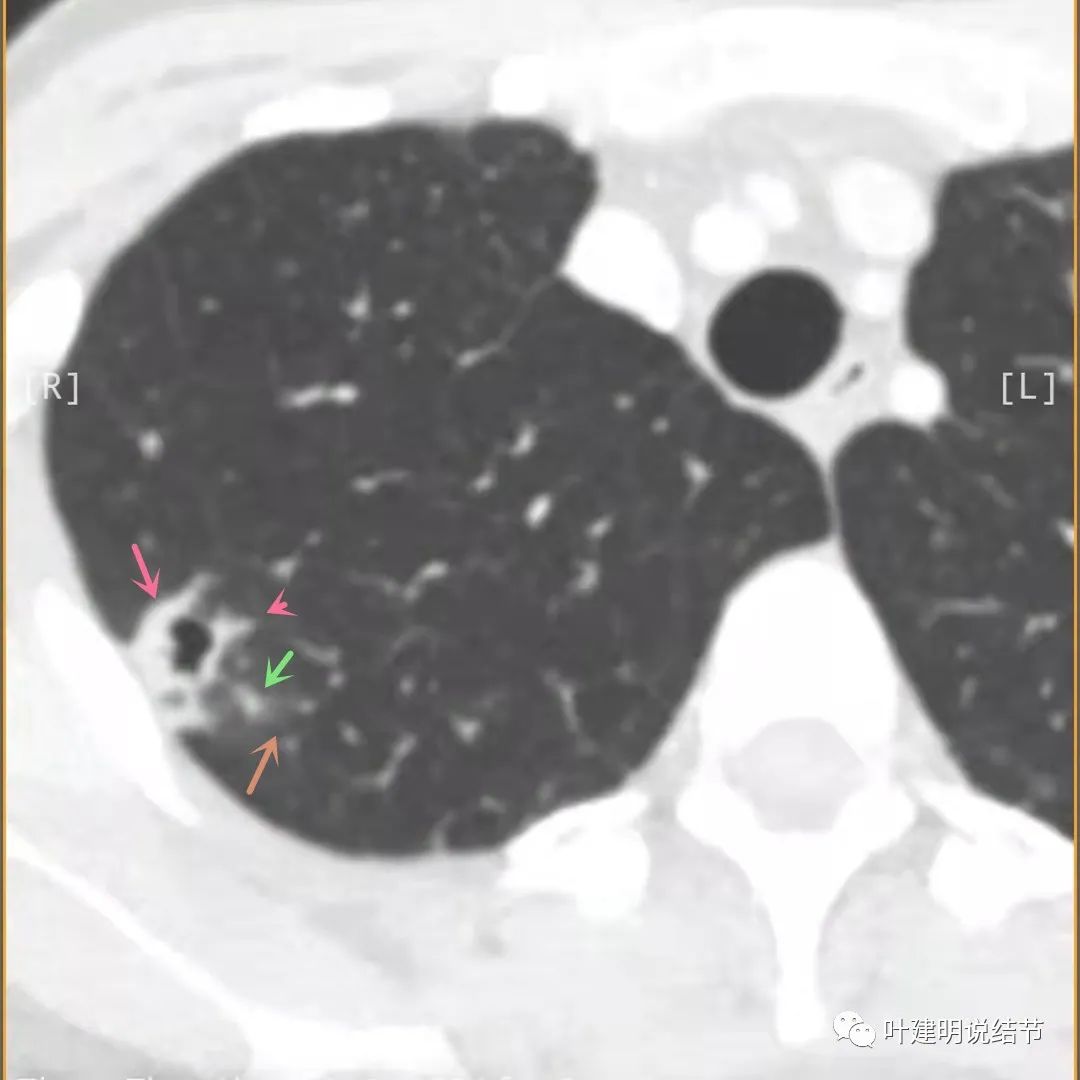

主病灶边界较清(红色箭头),实性部分密度过高(粉色箭头),病灶边缘向内凹,缺乏膨胀性(桔色箭头),病灶有空腔(黄色箭头)

邻近胸膜有增厚(蓝色箭头),主病灶的壁密度过高且整个壁密度都高(粉色箭头),旁边有磨玻璃影,散且模糊(砖色箭头)。内壁不均质(此不舒服)

邻近胸膜有增厚(蓝色箭头),主病灶囊壁密度过高(粉色箭头),内部有突起(细红色箭头),旁边有磨玻璃影,散且模糊(砖色箭头),中间有空腔,内壁有些区域又是光滑的

邻近胸膜有增厚(蓝色箭头),主病灶边缘较为平直,缺乏膨胀性(桔色箭头),实性部分密度过高(粉色箭头),旁边有磨玻璃影,散且模糊(砖色箭头)

病灶边缘较为平直,膨胀性不够(桔色箭头)